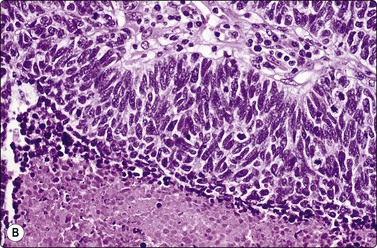

image image image

Fig. 8.28 High-grade neuroendocrine carcinoma; small cell carcinoma

(A, B) Smears showing ‘intermediate’ morphology. Loose aggregates of fragile cells with traumatization artifact and nuclear molding but some background cytoplasm (A, Pap, MP; B, H&E, HP). (C) Tissue section of resected peripheral stage 1 small cell carcinoma (H&E, HP).

image image image image image

Fig. 8.29 High-grade neuroendocrine carcinoma

Variable morphology including small cell and large cell patterns. (A) Low-power smear appearances of small cell carcinoma; (B) Higher-power examination shows some large cells with prominent nucleoli (A, H&E, LP; B, H&E, MP). (C,D) Tissue sections of resected peripheral stage 1 tumor showing areas of geographic necrosis and a predominance of large cells with prominent nucleoli (C, tissue section, H&E, LP, Inset, HP; D, tissue section, H&E, HP). (E) Positive immunostaining for chromogranin in resected specimen (E, tissue section, IPOX, HP).

Criteria for diagnosis

Small or medium-sized cells with little or no cytoplasm (larger than in sputum),

Dispersed cell presentation; some clusters, including some small tight groups,

Nuclear molding and engulfment; irregular nuclei,

Uniform finely or coarsely granular nuclear chromatin; small nucleoli,

Tear-drop cells, smeared cells and streaks of nuclear material,

Engulfment of apoptotic bodies,

Numerous mitotic figures.

This group of lung carcinomas is the most aggressive of the common types, having a mean survival of less than 6 months without treatment. Small cell carcinoma is virtually unheard of in non-smokers, while for carcinoid and atypical carcinoid the smoking association is much weaker. It is important to categorize this neoplasm accurately because, in general, chemotherapy rather than surgery will be used in management. In addition, chemotherapy regimens are different from those used for inoperable non-small cell carcinomas. This group is fairly homogeneous in terms of its biology but is more heterogeneous morphologically. Attempts at morphological subclassification have been made; however, the larger ‘intermediate’ and smaller ‘oat cell’ subtypes are not reliably separable by expert pathologists and do not have significantly different behavior or response to therapy. The latest WHO classification therefore does not subcategorize small cell carcinoma although it does recognize mixtures with other types of carcinoma.217

Cell pleomorphism is so distinctive that a diagnosis of malignancy is seldom in doubt (Figs 8.25-8.27). The most immediate impression is the absence or sparseness of cytoplasm rather than the small size of the neoplastic cell (Figs. 8.26 and 8.27). In fact, the cell nuclei may appear larger than similar cells in sputum and this may mislead one into making a diagnosis of non-small cell carcinoma. This difference in size between sputum and aspirated material is due to degenerative changes and shrinkage in sputum. It is sparseness of cytoplasm rather than size which is the most helpful initial clue in differentiating the lesion from other pulmonary carcinomas.

The combination of dispersal with clustering is also important, especially when other small cell neoplasms enter the differential diagnosis (Fig. 8.25). Lymphomas generally do not display such cell cohesion, although large fragments may be dislodged, and in some cases lymphoid cells may form clusters or packets.

Fragility of nuclei is emphasized by tear-drop cells or streaks of smeared nuclear material,226 and the close nuclear apposition and molding so commonly seen in sputum are also evident (Figs 8.26 and 8.27). Uniform coarsely granular ‘salt and pepper’ nuclear chromatin is also a well-recognized feature of this cancer in other sites, but one point of difference from sputum is the frequency of small nucleoli in aspirated material; they are less commonly seen in sputum. This may also be related to the better preservation of cells removed directly from tumor; small nucleoli are also often seen in bronchial brush material. Mitotic figures are usually easily found.